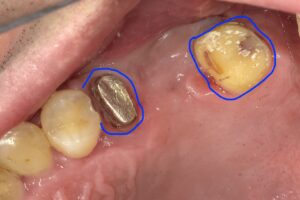

上の画像は銀色の棒が入っており既に神経をとっていることになります。

しかし上の画像の右の青丸部分は神経のある歯に

なります。

このぐらい削らないとブリッジを入れることができない

場合もあります。